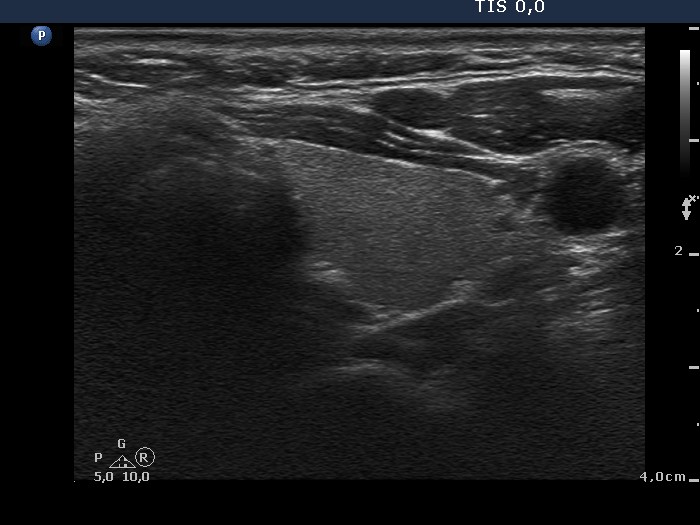

Ultrasonography. The thyroid was echonormal. There was a hypoechogenic lesion in the dorsal part of the right lobe. The nodule presented microcalcifications and hyperechogenic patches. No vascularization could be detected.